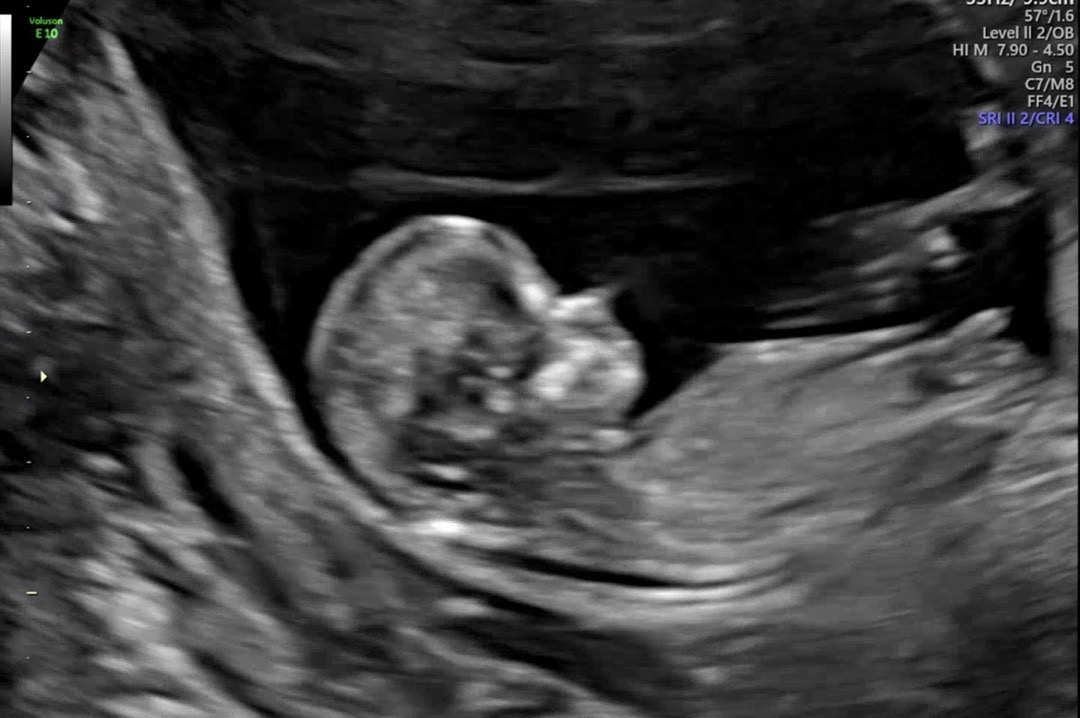

11주 5일 각도법 봐주실 수 있나요 💖?

11주 5일인데 각도법 봐주실 수 있나요 ?! 🥹🤍🤍